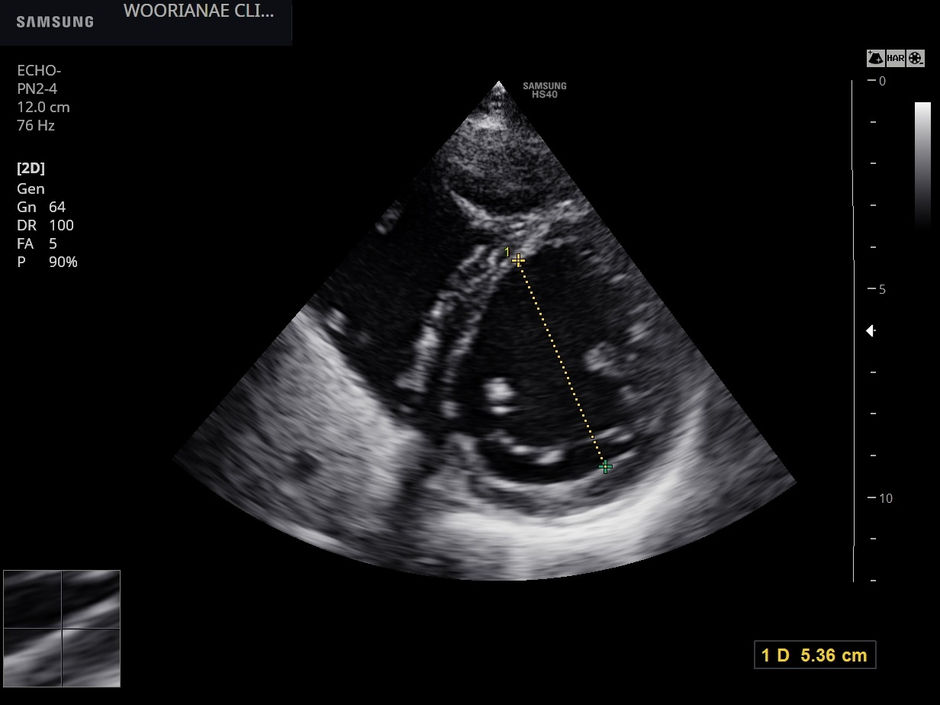

심잡음 평가에서 중등도 대동맥 판막 역류, 경도의 이첨판 협착... 대동맥 확장에 대해 상급병원 진료 - 동대문구 답십리, 장안동, 우리안애 우리안愛 내과

60대 후반 여자 본원에서 혈압약 투약하시는 분으로 과거에 간헐적인 화끈거림으로 갈색새포종 배제위한 24시간 소변검사 시행한적 있음. 이후 혈압약 투약 받던 분으로 이번 방문시 혈압 측정중 불규칙한 맥박이 느껴져 청진을 하니 뚜렷한 (grade...